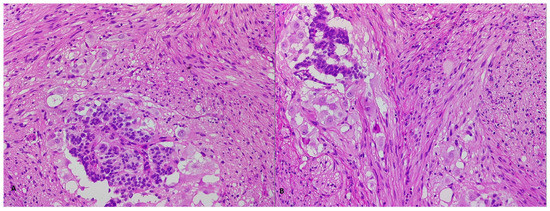

2. Case Report 1